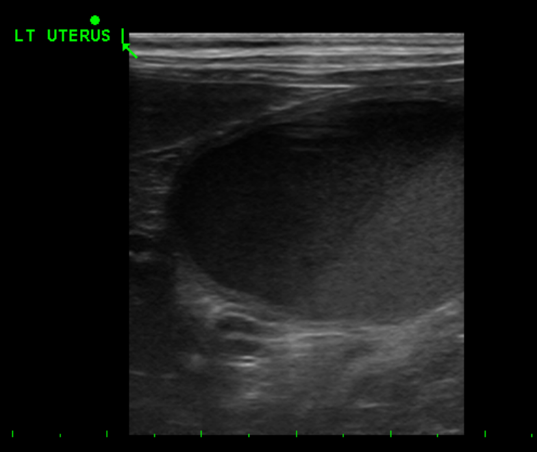

이후 시행한 초음파 검사에서는

➡ 양측 자궁각 내부에 echogenic한 액체(고름으로 추정되는 내용물)가

다량으로 차 있는 모습과 함께 자궁이 크게 확장된 상태가 확인되었습니다.